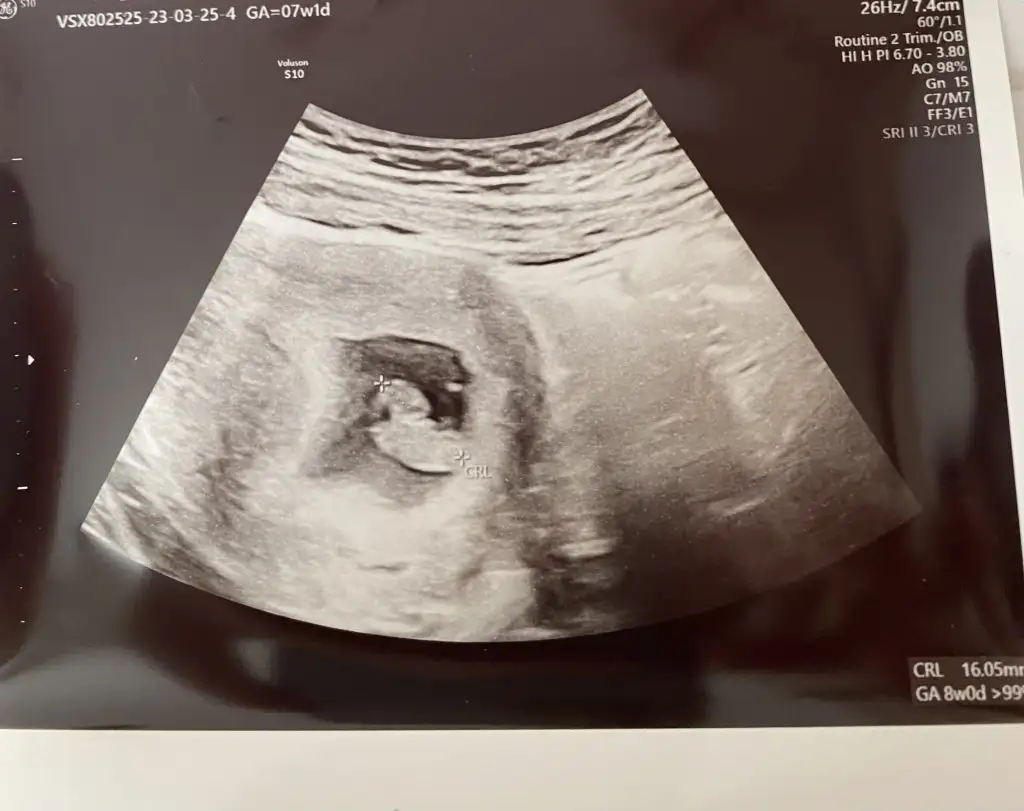

Ortadaki fotoda bebek 8 haftalık plasenta sağda yine teori tutuyor ( karından ultrason çünkü)